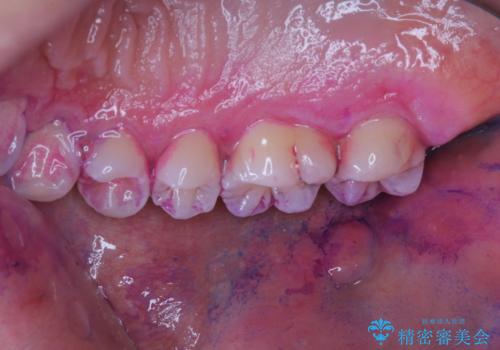

染め出しをして磨き残しのチェックと歯のクリーニング

染め出し液を使ってプラークを染め出すことにより、普段の歯みがきで磨き残している場所を目で確かめることができます。